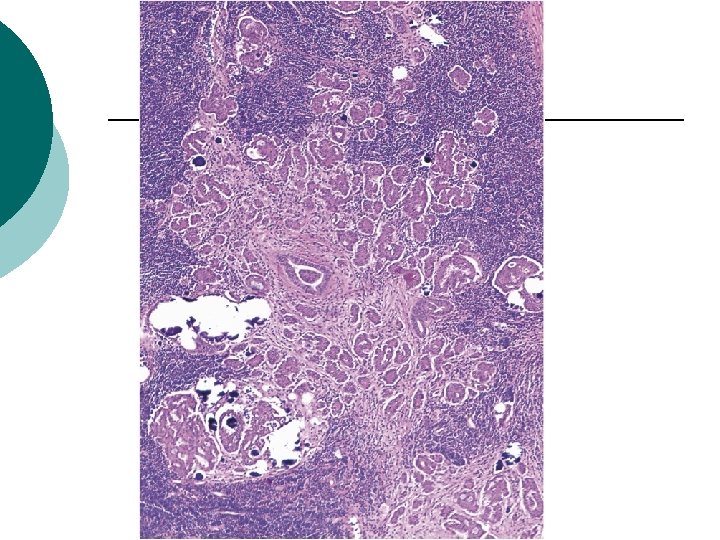

Micropapillary Architecture

Micropapillary Architecture ¡ ¡ ¡ 5/31 The number of nodes involved: 2 to 11 (mean, 4. 6), others : mean of 2. 1 (range, 1– 12) 3 of the 5 (60%) lymph nodes with micropapillary architecture also had an associated stromal reaction, compared with 2 of 26 (8%) without micropapillary architecture (P=0. 02). 4 of the 5 (80%) micropapillary cases had nodular aggregates (size from 2 to 8 mm), whereas only 2 of the 26 (8%) nonmicropapillary cases formed a nodular aggregate (1 mm in size) (P<0. 001). 3 (60%) were associated with endosalpingiosis, compared with 16 of 26 (62%) nonmicropapillary cases.

Micropapillary Architecture ¡ ¡ ¡ All 5 patients with micropapillary LNI had peritoneal implants. (2/5 invasive) Follow-up information: 2 AWD , 1 NED at 87 months following an abdominal wall recurrence at 74 months, and 1 was NED with no evidence of recurrent disease at 77 months, 1 LFU Disease-free survival versus LNI without this pattern : 50% vs. 82% not reach statistical significance (P=0. 22).